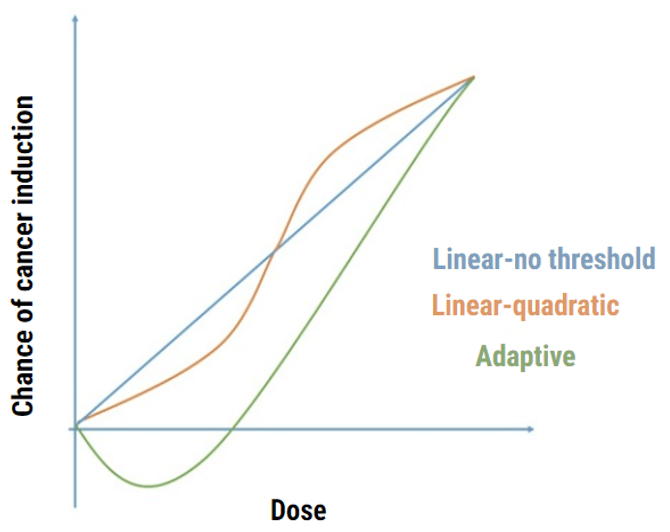

In your previous education, you were taught the bioeffects of radiation. CT technologists must be educated in the radiation bioeffects of the dose in CT. These effects are also classified as deterministic (non-stochastic) and stochastic.

Stochastic effects assume that the probability (not the severity) of the effect occurs depending on the dose. As the dose increases so do the probability and there is NO threshold dose for these effects. If you recall, no threshold means that any amount of radiation can cause some type of effect.

Deterministic effect, such as skin erythema and cataracts, have a threshold dose for which these responses will not occur. Deterministic effects deal with the severity, not the probability of a response.